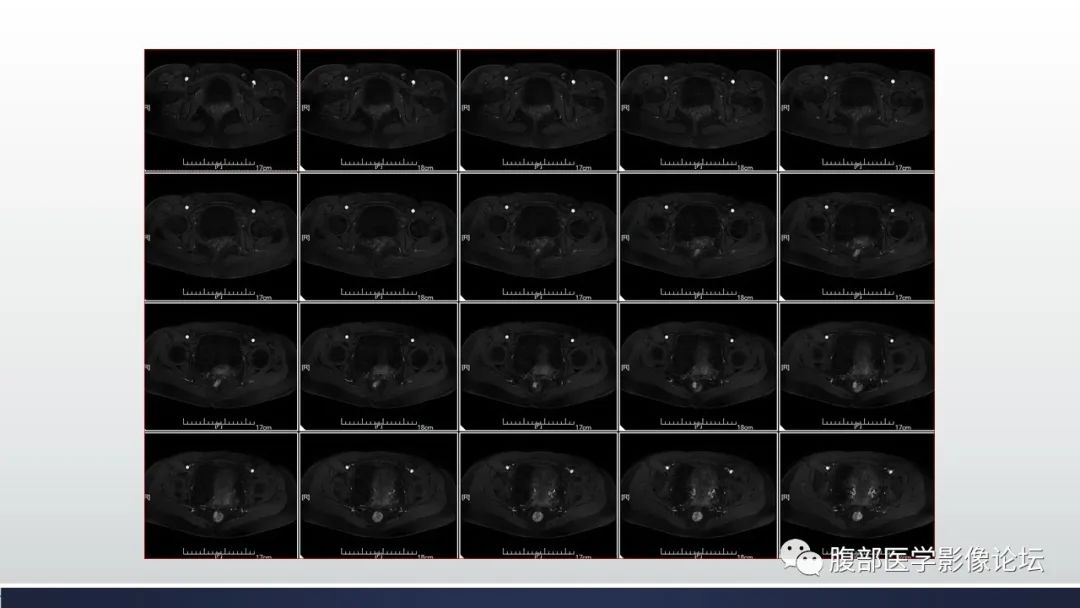

【病例】子宫内膜透明细胞癌1例MR-13

【病例】子宫内膜透明细胞癌1例MR-14

【病例】子宫内膜透明细胞癌1例MR-15

【病例】子宫内膜透明细胞癌1例MR-16